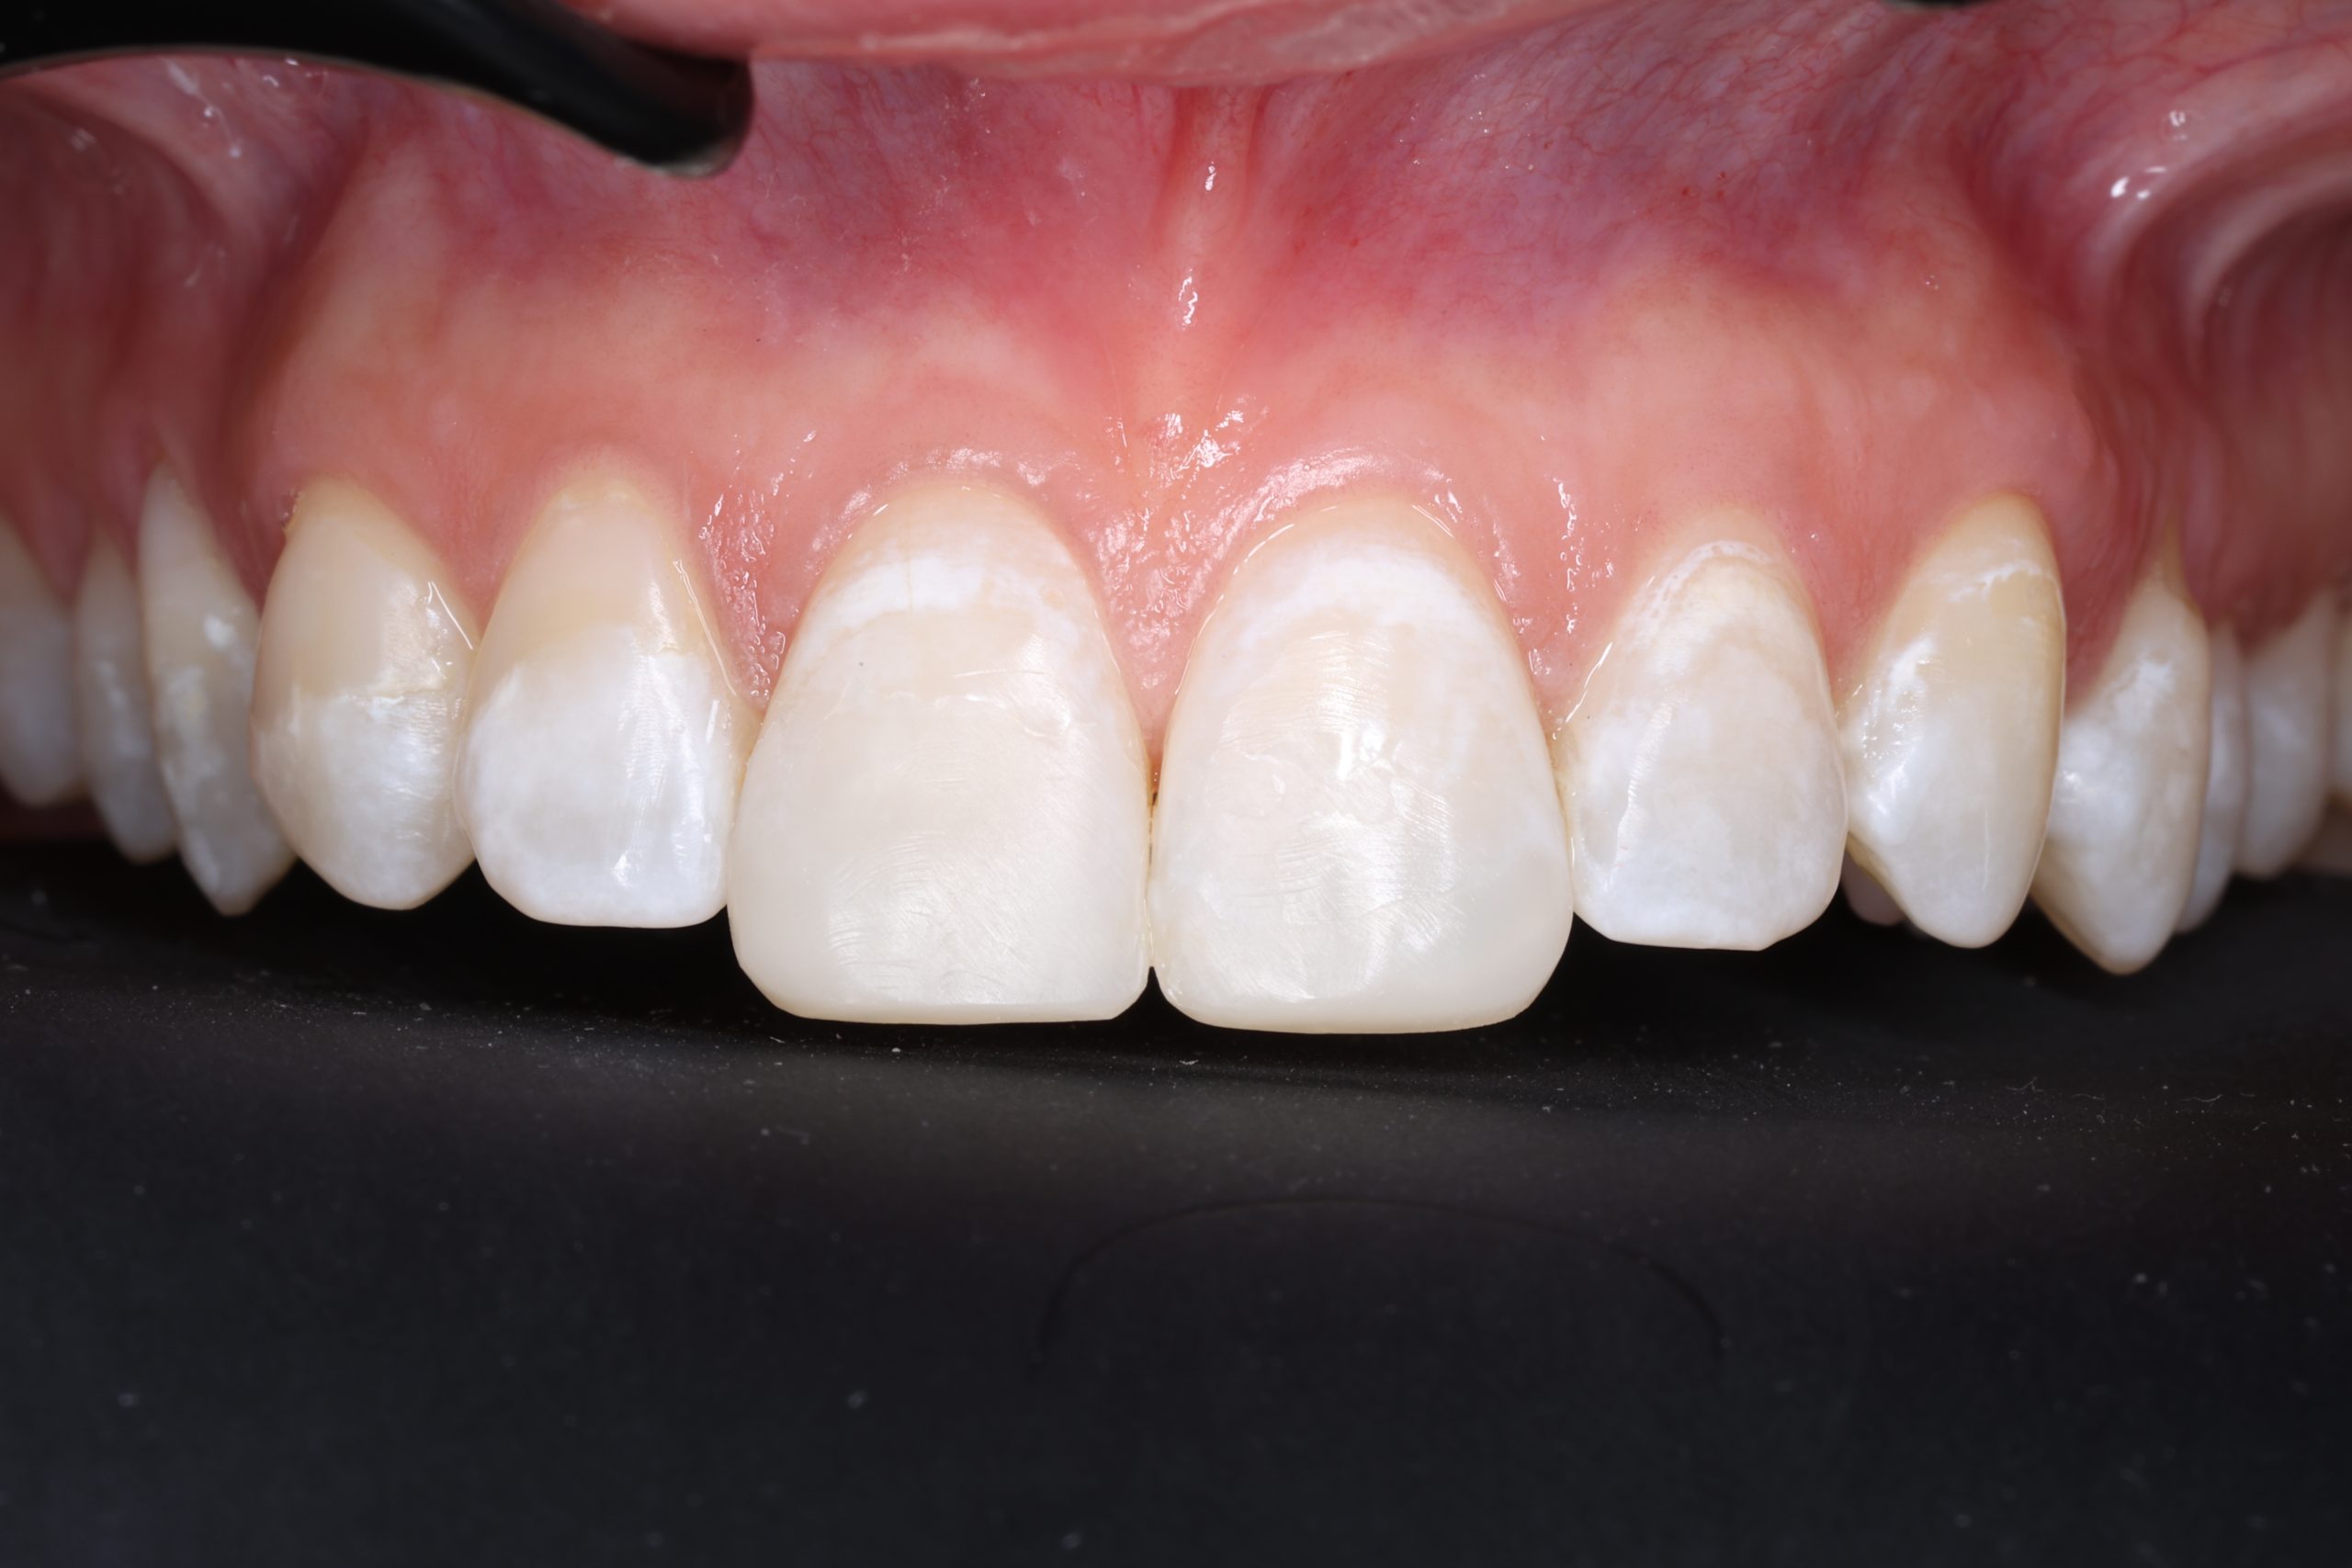

5. Final Polishing and Bite Adjustment

We contour and polish the surface to a high gloss and ensure your bite feels natural in all positions.

Aesthetic and Natural-Looking

The material matches your enamel, blending into the smile with virtually invisible transitions.